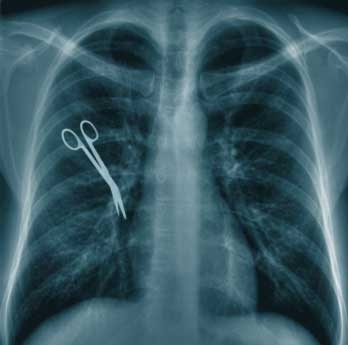

With the ever increasing hype surrounding lawsuits against medical practitioners in South Africa, this is no longer restricted to the soap operas from day time television made in sunny L.A., but has become more commonly found here in South Africa. Medical malpractice suits against plastic surgeons were the primary leading news items which grabbed the headlines; more recently, obstetrics and gynaecology suits have featured more prominently in the local media and, as a result, become more lucrative areas of litigation. For example, the Medical Protection Society recently settled a single Gynaecology claim, worth R27 million. While a number of high profile settlements in favour of patients have established the trend in South Africa, it has been exacerbated by attorneys now actively pursuing medical negligence claims due to the high earning potential that they offer. With an 18% increase in the number of medical malpractice claims in excess of one million Rand over the last decade plus a 900% increase in medical malpractice claims over five million Rand one can certainly understand the rash of radio and TV advertisements calling on patients to seek legal assistance at the hint of malpractice. The result of this legal onslaught is that the Medical Protection Society, which assists doctors with legal matters, has recently been swamped with a backlog of more than a 1000 complaints of negligence against South African medical practitioners. Very few doctors have that type of money to pay out for malpractice claims whichis why it is so important to obtain insurance should this scenario ever crop up. The Medical Protection Society of South Africa recommends that all medical practitioners take out medical malpractice insurance to cover any malpractice suit that might occur, making this an absolute necessity. It is simply not worth the risk; Studying towards a medical degree for years on end; sacrificing time, money and every thing that presents an obstacle to obtaining your medical degree; to simply lose everything by not having the medical malpractice cover that will protect you against such eventualities occurring would be negligent. Humans make mistakes – but don’t make the mistake of not insuring against medical malpractice as this will be one mistake that could take away everything you have worked for. In today’s society it is important to ensure that you have the right cover protecting your practice from occurrences that could financially destroy you.